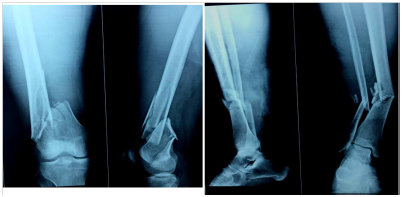

Figure 1 A-B, Preoperative x-rays (AP and lateral views) showing a Fraser type IIb floating knee.

Figure 2 A-B, same fracture treated by ORIF by condylar locking plate and IM nailing of tibia respectively.